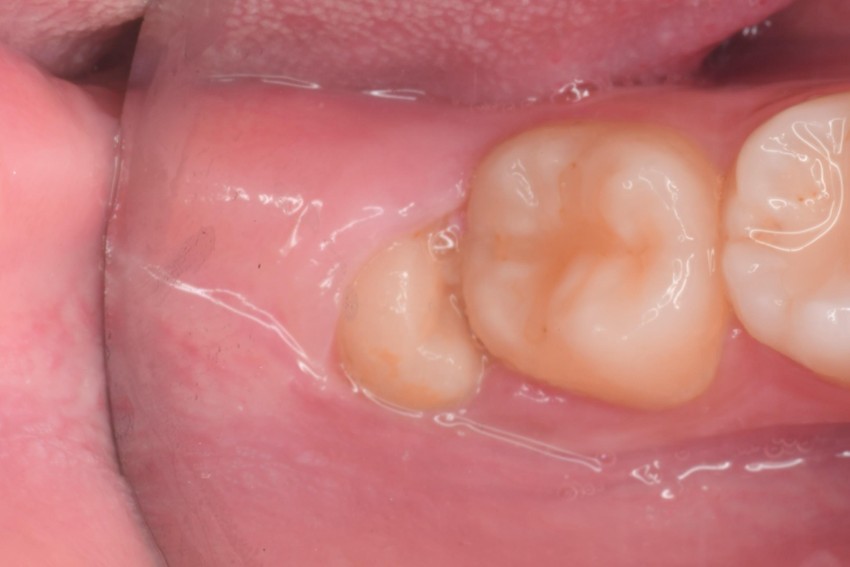

治療前,左下阻生齒深度蛀牙